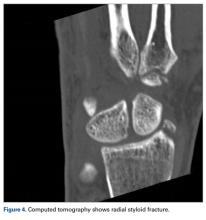

A fit and healthy 30-year-old male software professional fell down stairs, landed on his nondominant right hand, and sustained a high-energy wrist injury. The patient also sustained a concussion, without focal neurologic deficit, and was unable to recall the exact mechanism of the wrist injury (there were no other witnesses). Radiographs of the right wrist in the emergency department showed only a nondisplaced fracture of the neck of the second, third, fourth, and fifth metacarpals and a nondisplaced fracture of the radial styloid.

Later, however, the hand surgery team evaluated the radiograph as well as computed tomography (CT) scans and found a translunate, transradial, transtriquetral, transtrapezoid perilunate dislocation of the wrist with multiple metacarpal neck fractures ( Figures 1-5 ).The next day, with the patient under general anesthesia, an attempt to reduce the perilunate dislocation by manipulation was unsuccessful. Open reduction and internal fixation (ORIF) were performed through a dorsal approach; the perilunate dislocation was reduced and stabilized with lunocapitate 1.2-mm Kirschner wire (K-wire). The scapholunate and lunotriquetral ligaments were found to be intact, and the significantly displaced triquetral fracture was treated with internal fixation involving 2 minifragment screws ( Figure 6 ).

Perilunate injuries have been missed in busy emergency departments and orthopedic practices. An estimated 25% of such injuries can be missed on initial presentation. 8 In the present case, fracture of the radial styloid provided a clue to possible more complex carpal injuries involving the scaphoid, lunate, or scapholunate ligament, as Graham 4 suggested with the concept of the “transverse pattern” of force transmission. In this case as well, the injury was initially missed, and its extent became evident only with CT. Therefore, emergency teams should have a very low threshold for suspecting and evaluating high-energy wrist injuries.